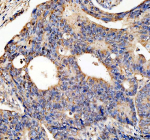

IHC analysis of NCOA2 using anti-NCOA2 antibody. NCOA2 was detected in a paraffin-embedded section of human prostate hyperplasia cancer tissue. Heat mediated antigen retrieval was performed in EDTA buffer (pH 8.0, epitope retrieval solution). The tissue section was blocked with 10% goat serum. The tissue section was then incubated with 2 ug/ml rabbit anti-NCOA2 antibody overnight at 4oC. Peroxidase Conjugated Goat Anti-rabbit IgG was used as secondary antibody and incubated for 30 minutes at 37oC. The tissue section was developed using an HRP secondary and DAB substrate.